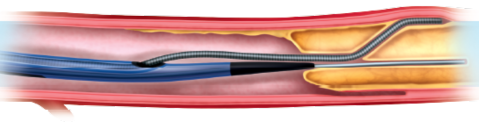

RECROSS

A UNIQUE SOLUTION FOR GUIDE WIRE REDIRECTION AND SUPPORT

The dual OTW lumen of the ReCross microcatheter with two completely separate over the wire lumens and three distal exit ports allow unique complex PCI procedural techniques as Antegrade Dual Access (ADA), Subintimal Guidewire Redirection (SGR) and simultaneous hematoma decompression in the subintimal space and guidewire probing